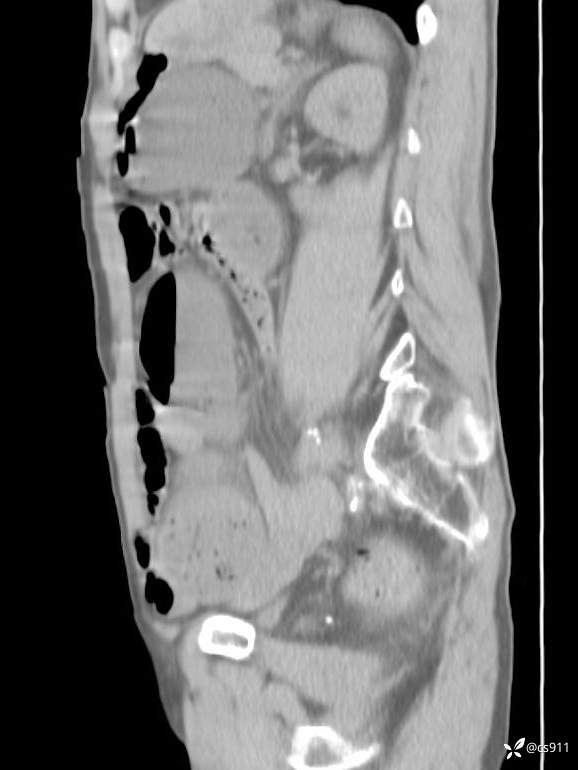

急腹症之急诊CT,原因?答案公布

男,77岁,腹痛、腹胀伴恶心呕吐1天。呕吐胃内容物,非喷射性呕吐,有咖啡色样胃内容物,诉有胃穿孔病史。查体:全腹平,下腹部压痛,全腹无反跳痛,叩诊呈浊音,移动性浊音阴性,肠鸣音减弱,1-2次/分。肛检:直肠未扪及明显肿物,可触及大量粪块。

血淀粉酶(AMY) HH 1859 U/L 35-135